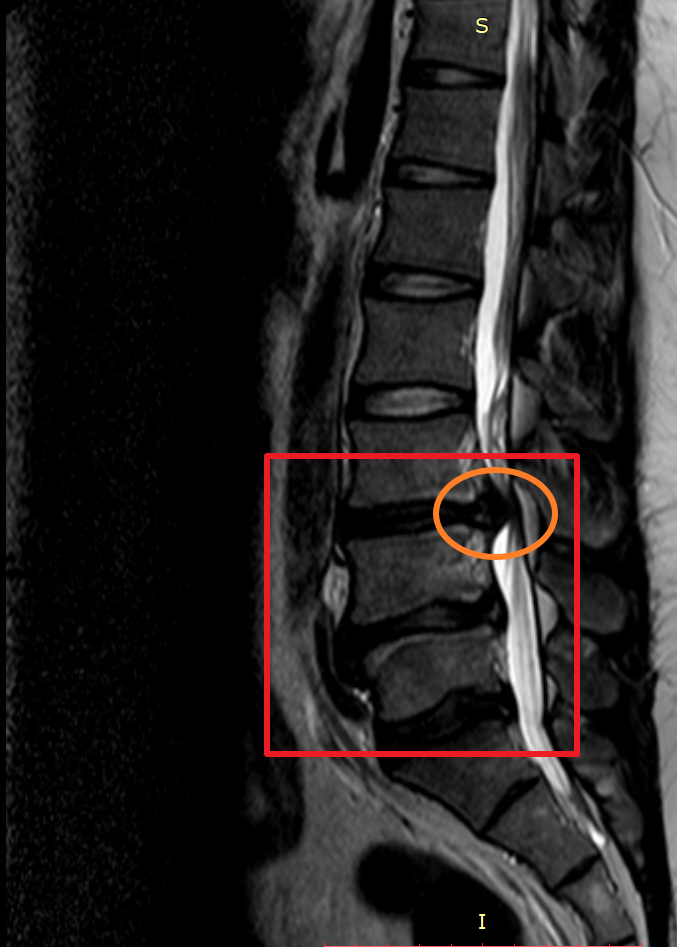

마지막 허리디스크 MRI는 2020년에 촬영했습니다. 마찬가지로 사진을 보시면 최초 발병한 허리디스크 첫 번째 동그라미는 흡수가 된 게 눈에 보일 정도였으나 4년뒤엔 두 번째 동그라미와 세 번째 동그라미 디스크가 많이 튀어나와 신경을 누르고 있는 게 보입니다.

하지만 MRI 상 표시된 부분을 보면 첫 번째 허리디스크가 튀어나왔던 부분이 흡수된 게 확실히 보이며 이제는 다른 부분에 허리디스크가 눌려 신경을 누르고 있는 게 보입니다.

MRI에 표시된 부분만 놓고 본다면 허리에 데미지를 주지 않고 잘 관리하는 상황에서 분명 튀어나온 허리디스크가 흡수 되는 건 맞는 이야기이며 허리디스크가 흡수되는 시간이 최소 6개월 이상으로 굉장히 오래 걸린다는 겁니다.